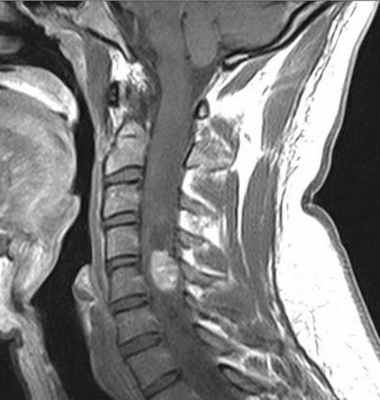

Гемангиобластома наблюдается заметно реже (около 2-6%), чем астроцитома и эпендимома. Встречается чаще в среднем возрасте. Примерно в трети случаев является проявлением болезни Гиппеля – Линдау, тогда она наблюдается у более молодого контингента пациентов и может быть множественной. Спинальная гемангиобластома сопровождается реактивной кистой, по чертам напоминающаю сирингомиелитическую.

При МРТ позвоночника обнаруживается узел изо- или гипоинтенсивный спинному мозгу на Т1-взвешенных МРТ и обширная киста ликворной или несколько повышенной интенсивности сигнала. На Т2-взвешенных МРТ иногда видны расширенные сосуды, особенно вдоль задней поверхности спинного мозга. После МРТ с контрастированием узел становится ярким, четко очерченным.

МРТ шейного отдела позвоночника. Интрамедуллярная гемангиобластома. Сагиттальная Т1-взвешенная МРТ после контрастирования.